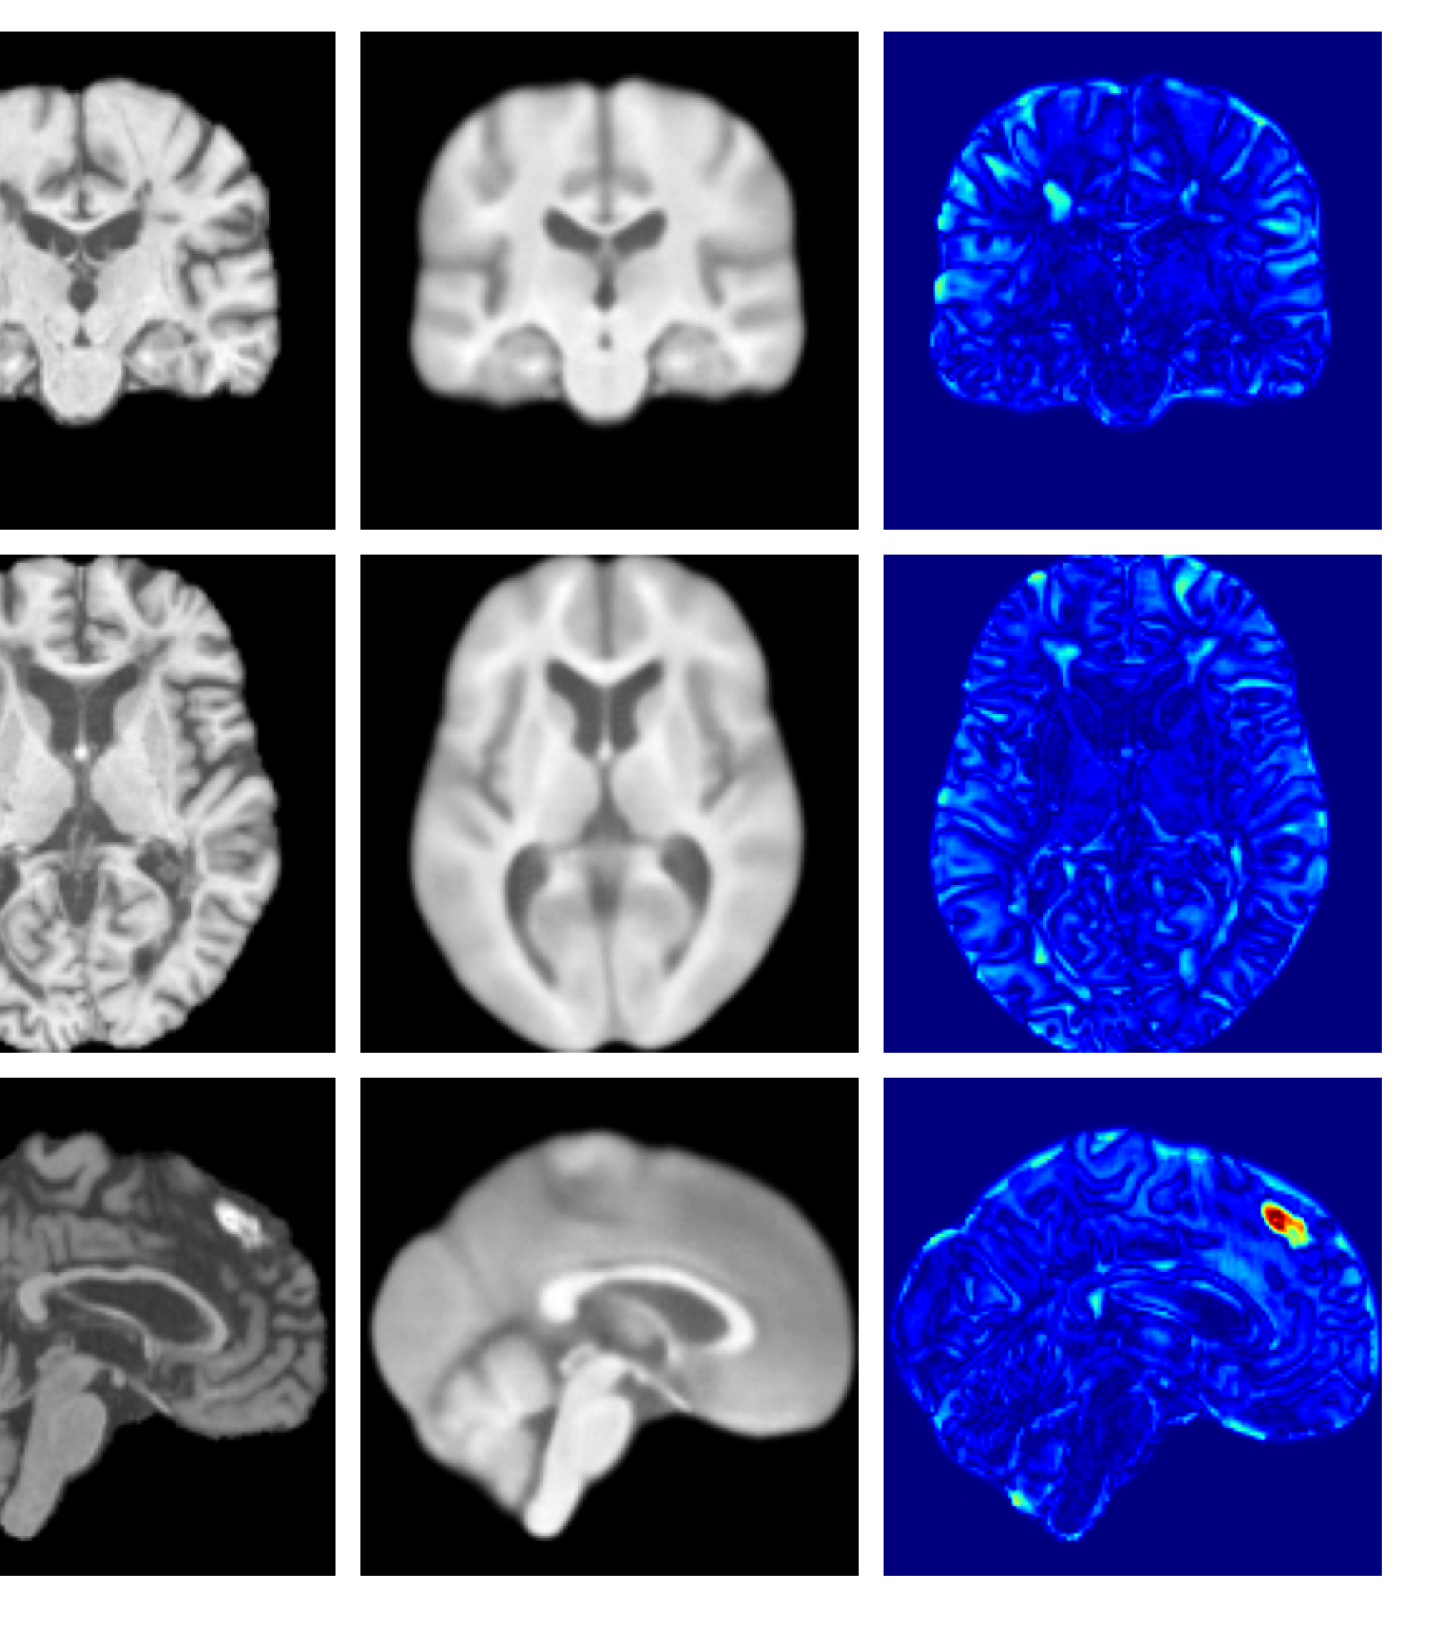

Figures 8 and 9 are enlarged versions of Figures 3 and 4 respectively, with the latter now including results from all compared methods. Figure 10 provides example reconstructions and anomaly maps for an AD subject from the ADNI disease cohort.

Refer to caption

(a) Input

Figure 9: Enlarged example reconstructions and anomaly maps for a sample from the disease cohort of the XXXH dataset. The lesion region is indicated in the original image by the red box.